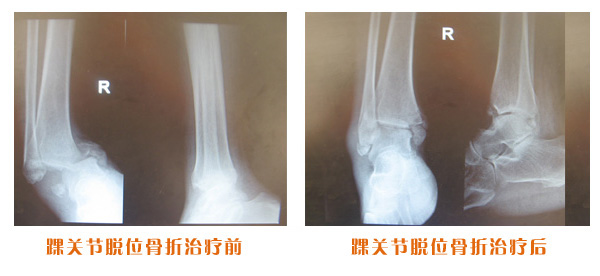

肥城市安駕莊梁氏骨科醫(yī)院是一所以梁氏手法正骨配合膏藥為特色的現(xiàn)代化??漆t(yī)院。

梁氏骨科術(shù)始創(chuàng)于清雍正年間,歷經(jīng)八代,至今已有三百年歷史。據(jù)1929年泰安縣志載“梁瑞圖先生,字增生,號蓮峰,安駕莊人,精岐黃并發(fā)明接骨,凡跌打車凡跌打車軋皮不破而碎骨者......【詳細】 |